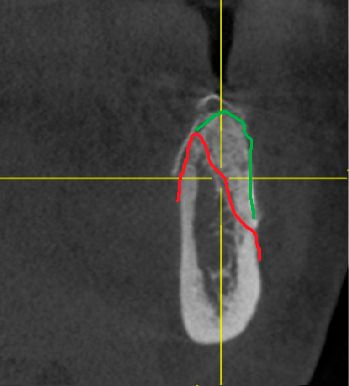

У молодой девушки после неоднократных попыток восстановления бокового резца консервативными методами произошел перелом корня. У пациентки было важное пожелание-не оставаться без зуба ни одного дня. Проведено атравматичное удаление бокового резца, одномоментная установка имплантата Nobel Parallel. Ортопедом установлена временная коронка в день операции.